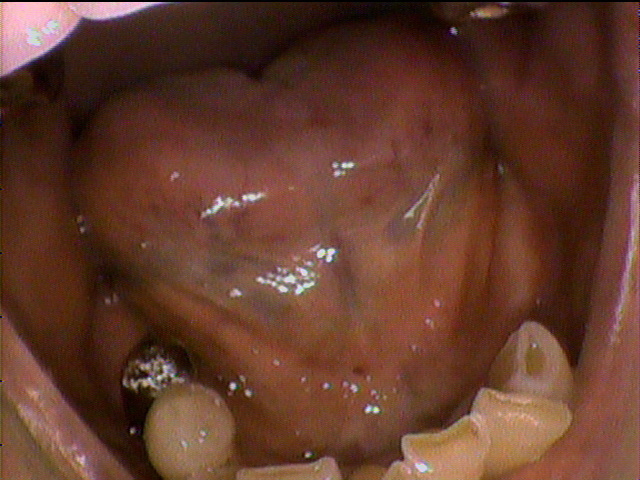

本日、出来上がりました自費の部分入れ歯ー下顎メタルプレートの症例です。

81歳の女性OUさんはとけも若々しいかたで、上下ともに、ぶぶん入れ歯ですが、今回は下顎の左右の奥歯のメタルプレートの入れ歯を新しく作りました。

自費によるメタルプレート義歯で、薄く丈夫な義歯として、とても舌感の良好な状態にすることができ、さらに自由な義歯の設計ができるため、残っているはにかける針金は白金加金で作成し、残存歯にやさしい設計となっており、舌に触れるバー部分はコバルトクロム合金で、丈夫に薄く作ってあります。

(参考代金;30万円)